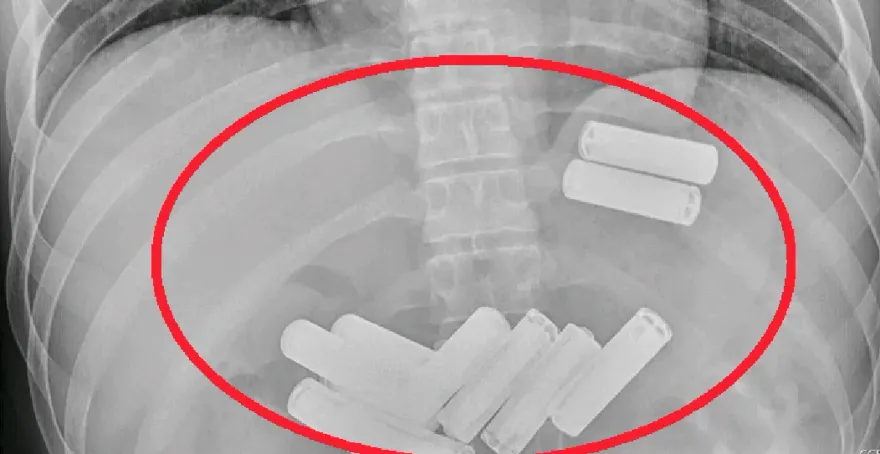

誤食異物

電池

吞下肚

食道撕裂